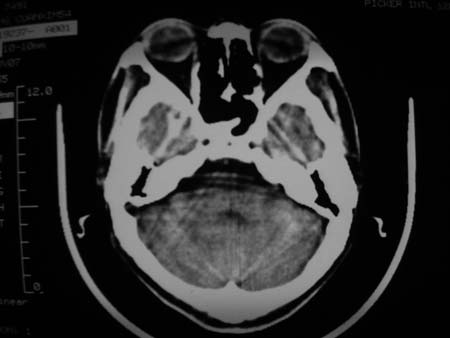

男,54岁,十天前被钢管打伤头顶部,现自述头部不适,视物模糊,并于两天前发觉右枕部有包块,既往未有明显异常.

颅骨多处骨质不完整,内板变薄,右侧额颞部局部呈“穿凿样”骨质缺损,相应区硬膜外密度略增高。多考虑:骨嗜酸性肉芽肿!

颅骨多处骨质不完整,内板变薄,右侧额颞部局部呈“穿凿样”骨质缺损,相应区硬膜外密度略增高。多考虑:骨髓瘤或骨嗜酸性肉芽肿!

颅骨多处骨质不完整,内板变薄,右侧额颞部局部呈“穿凿样”骨质缺损,缺损骨质边缘锐利无硬化,相应区硬膜外密度略增高。多考虑:骨嗜酸性肉芽肿!

颅骨多处骨质不完整,内板变薄,右侧额颞部局部呈“穿凿样”骨质缺损,相应区硬膜外密度略增高。多考虑:骨髓瘤或骨嗜酸性肉芽肿!10天前受伤,不会在2天前才发现头部包块,估计与外伤无关.